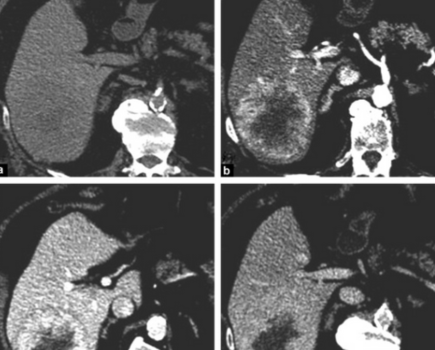

LI-RADS : Quelles combinaisons de critères majeurs sont les plus utiles ? - Le LI-RADS peut-il diagnostiquer le CHC chez les patients sans cirrhose et sans hépatite virale B ?

Pilier du diagnostic non invasif du carcinome hépatocellulaire, le LI-RADS repose sur des critères majeurs dont les combinaisons sont utilisées quotidiennement en pratique. Pourtant, la contribution diagnostique respective de ces associations reste discutée, notamment aux frontières entre les catégories. Des travaux récents viennent préciser la performance réelle de ces combinaisons et interrogent l’applicabilité du LI-RADS au-delà de sa population cible historique.